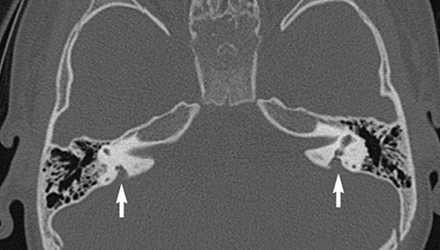

SLC26A4基因定位于人類染色體7q31,SLC26A4基因和大前庭導(dǎo)水管綜合征相關(guān)突變位點的發(fā)現(xiàn),證實SLC26A4是大前庭導(dǎo)水管綜合征的責(zé)任基因。

我們平時提到的“一巴掌打聾”、“一跤摔聾”其實都與SLC26A4基因突變有關(guān),絕大多數(shù)大前庭導(dǎo)水管綜合征都是SLC26A4基因突變?nèi)堑牡湣?/p>

SLC26A4基因編碼一種叫“Pendrin”的跨膜轉(zhuǎn)運蛋白,在機體離子成分平衡的維持中發(fā)揮重要作用。

在內(nèi)耳,Pendrin表達(dá)于內(nèi)淋巴管、內(nèi)淋巴囊、橢圓囊、球囊等處,異變的蛋白將對這些結(jié)構(gòu)的正常生理功能產(chǎn)生影響,引發(fā)聽損。

SLC26A4基因突變導(dǎo)致的大前庭導(dǎo)水管綜合征的典型表現(xiàn)為兒童時期的聽力損失,90%的患者為雙側(cè)性,聽力損失程度不一,可表現(xiàn)為接近正?;蛑?極重度。

病程可為穩(wěn)定性、進行性或波動性,聽力可逐步下降至全聾;跌倒、撞擊等行為或無外界影響都可能引發(fā)聽力的下降。